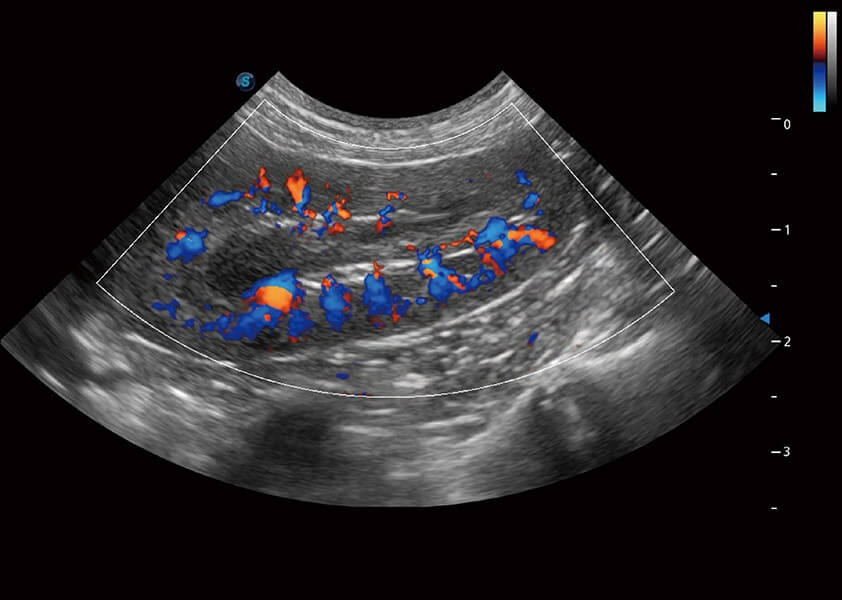

ProPet 60 作为一款高端台式动物超声设备,为动物医生的日常诊断提供了一系列贴合动物临床需求、解决临床实际问题的高级成像功能。凭借全系列高清探头,满足医生对腹部、心脏、生殖、浅表、肌骨等成像的所有需求,切实帮助您提升检查效率,提高诊断信心。

兽用彩色多普勒超声诊断系统